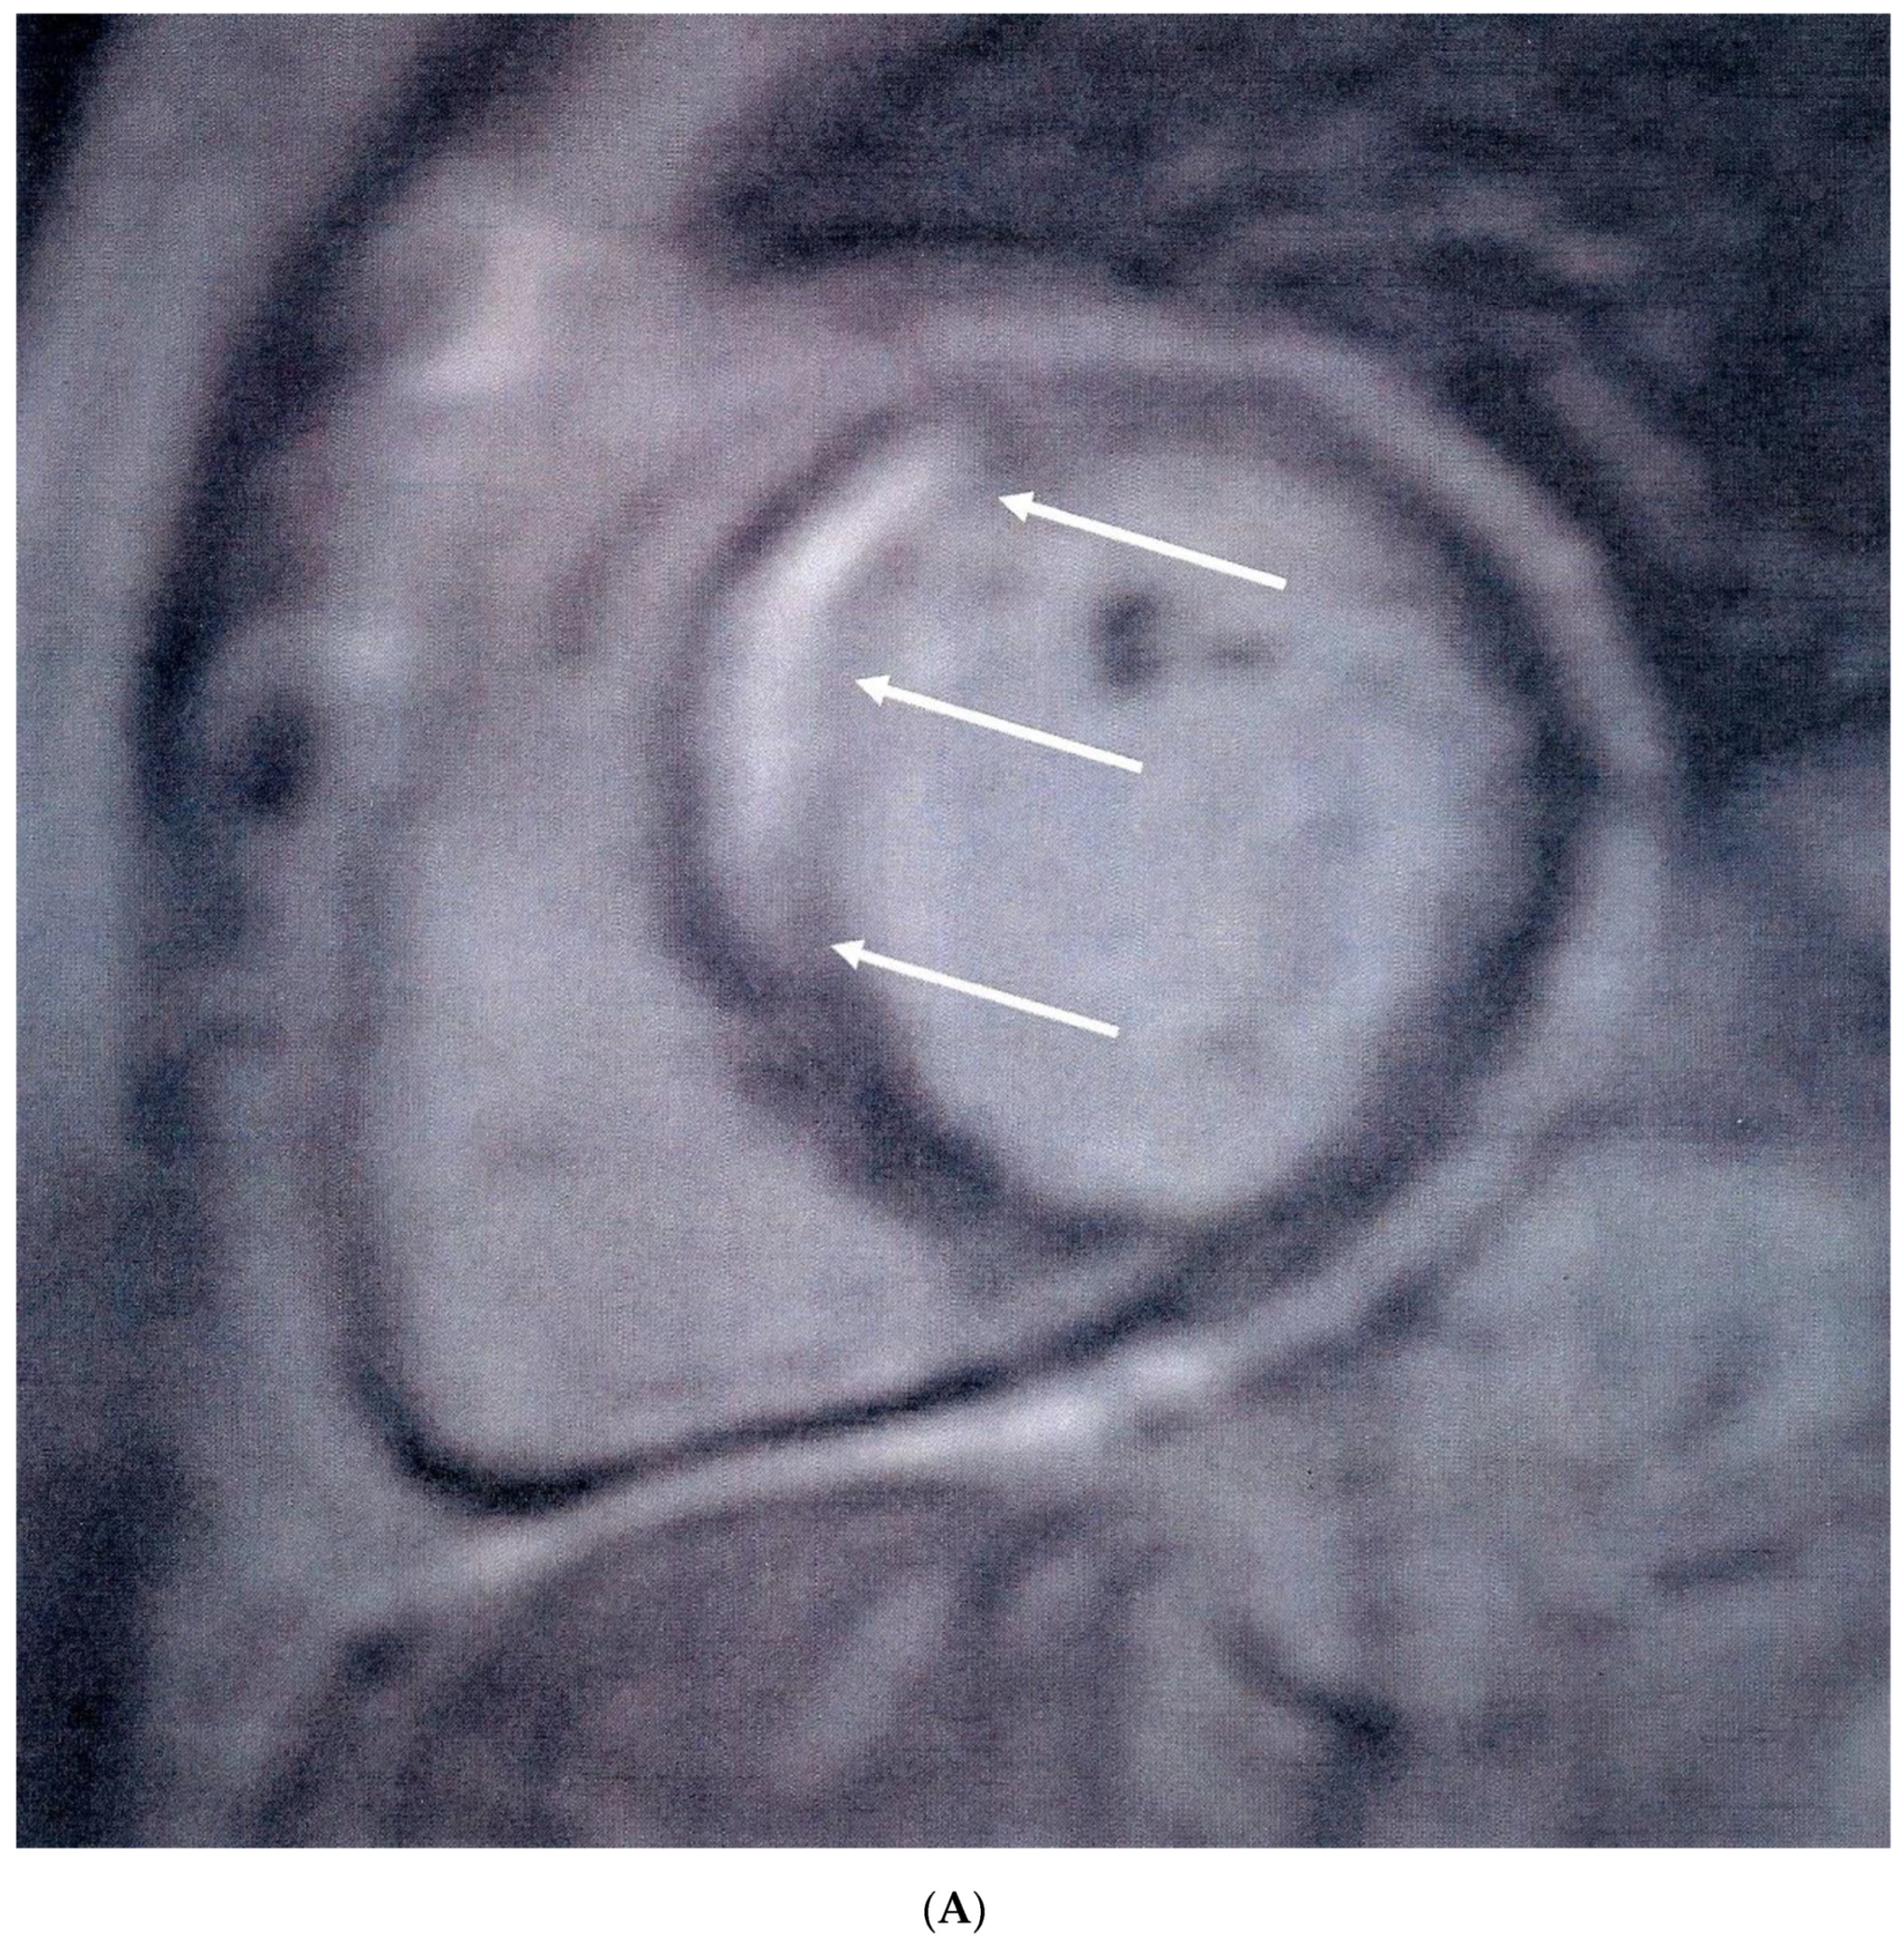

Median MPRI was significantly lower in APS patients compared to healthy controls [1.48 (0.9–1.9) vs. 2.7 (2.2–3.2), p < 0.001]. Sixteen (36%) APS patients had visible areas of myocardial scar, expressed as LGE, compared to none of the healthy controls (p < 0.001). Myocardial scar following the distribution of coronary arteries was identified in nine (20%) patients (five in the anteroseptal and four in the inferolateral LV wall) (Figure 1A), while diffuse subendocardial fibrosis (DSF) (Figure 1B) was identified in seven (16%) patients. In patients with a positive LGE, the median LGE values expressed as percentage of LV mass were 4.5 (3.5–7.5). Coronary angiography was performed in 12 of the 16 APS patients with positive LGE, with macrovascular (obstructive) CAD identified only in two patients, one of which subsequently underwent angioplasty of the left anterior descending artery. Three of 10 patients with otherwise normal coronary angiography findings had abnormal LVEF values (<55%) and concomitant low MPRI values below the median of the APS group (<1.48).

Figure 1. (A) Short-axis inversion recovery sequence showing septal myocardial scar (arrows), following the distribution of the left anterior descending artery, indicative of myocardial infarction. (B) Short-axis inversion recovery sequence showing diffuse subendocardial scar (arrows) due to microvascular disease.